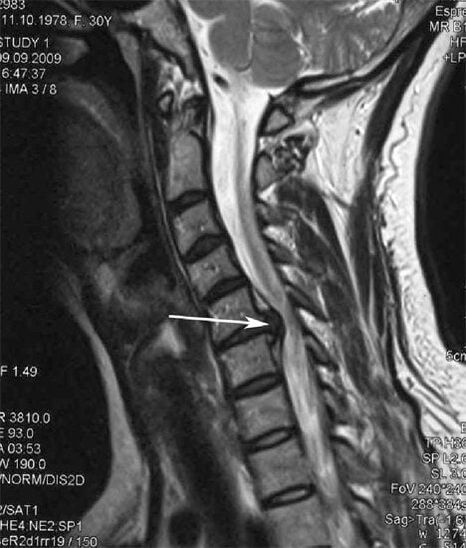

Nelle fasi iniziali, l'osteocondrosi viene rilevata mediante risonanza magnetica. Successivamente, la patologia può essere diagnosticata mediante radiografia. Nelle radiografie della colonna cervicale si notano una riduzione della distanza tra le vertebre, cambiamenti patologici nelle articolazioni delle faccette e osteofitosi.

Molte persone si lamentano di non riuscire a girare il collo a causa del forte dolore quando improvvisamente sollevano qualcosa di pesante. Questo fenomeno indica lo sviluppo di un'ernia del disco. La causa del dolore alla schiena, al collo e agli arti superiori è il pizzicamento di una delle radici nervose che escono dal midollo spinale.